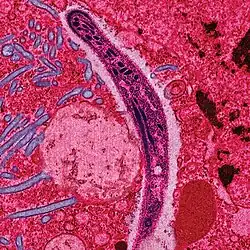

![]() Esporozoito de Plasmodium | ||

Todas las especies de este grupo tienen una etapa infecciosa (el esporozoito) que posee un complejo apical, que da nombre al grupo. El complejo apical es un orgánulo situado en una punta de la célula que posee tres estructuras distintivas: un conjunto de microtúbulos dispuestos en espiral (el conoide), un cuerpo secretor (las roptrias) y una o más bandas de microtúbulos (el anillo polar). Puede incluir también vesículas secretoras (las micronemas) rodeadas por uno o dos anillos polares.[4] El complejo apical le permite al organismo la entrada en la célula huésped combinando la acción perforadora del conoide con las secreciones químicas de las roptrias. Además del complejo apical, existen unos orgánulos esféricos secretores situados alrededor de la célula (denominados gránulos densos), que actúan después de la penetración en la célula huésped, persistiendo durante varios minutos. Sobre el resto de la célula, a excepción de una pequeña boca llamada microporo, la membrana se apoya en unas vesículas denominadas alvéolos corticales, formando una estructura semirrígida.